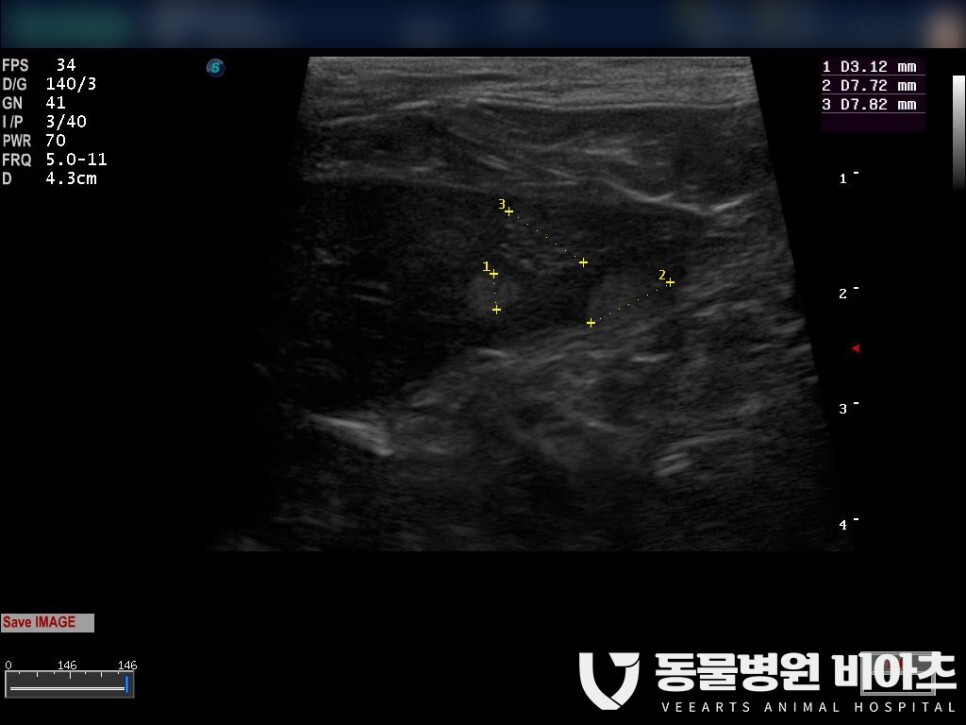

검사 결과는 초음파상 보이는 것처럼

안타깝게

종양이 발견되었습니다.

비장의 이상 여부를 확인할 수 있는

가장 좋은 검사 방법은 복부 초음파 검사입니다.

실질의 질감(texture)이나 모양을 확인할 수 있습니다.